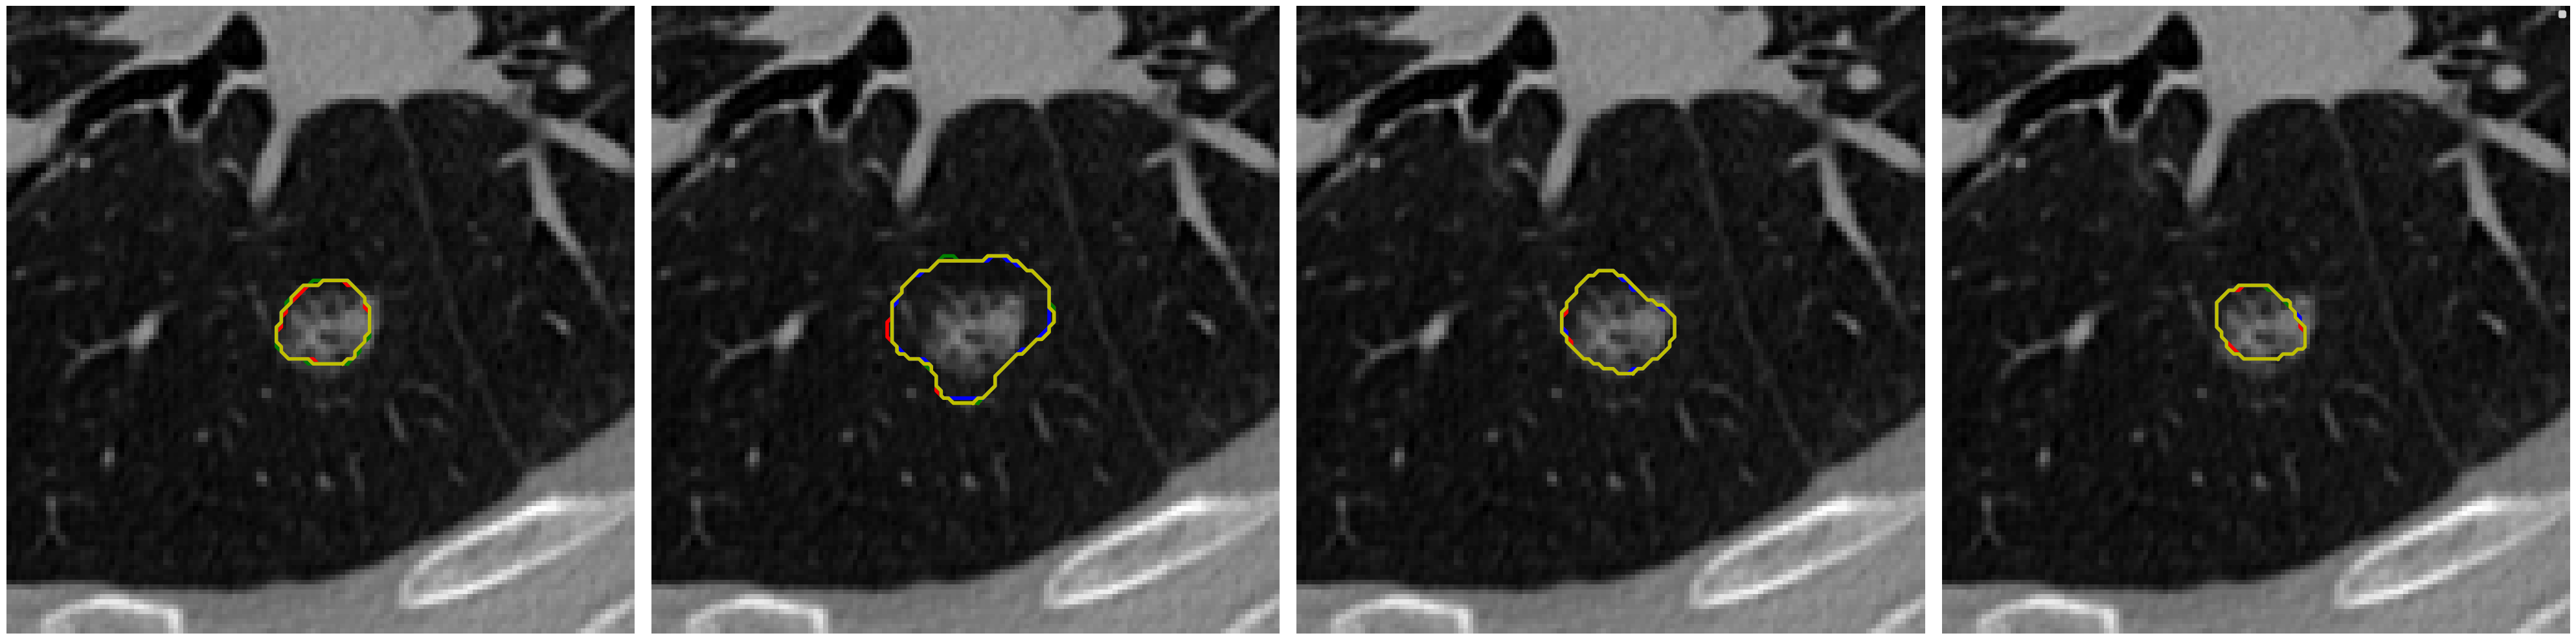

Visual comparison of segmentation results.

We provide visual comparisons of the segmentation results of all methods on the NPC dataset in Fig. 9 and Fig. 10, where different colors indicate the segmentation is obtained by different expert annotators. The segmentation results of ProSeg are more diverse and personalized than those of other methods. The segmentation results of ProSeg are more consistent with the ground truth while maintaining diversity among the generated segmentations. The results demonstrate that ProSeg effectively captures expert-specific characteristics and generates diverse segmentation results. For some methods, the segmentation from all the experts is the same, which means the diversity is poor. In Fig. 6(b), the second row shows the segmentation from our ProSeg, the third row shows the segmentation from the DPersona (stage 1) and the fourth row shows the segmentation from the DPersona (stage 2). For the second image, in the gold standard, three experts give segmentation containing two separate parts. Our ProSeg captures the character, while other models can hardly capture this difference, and generation methods can not tell which expert gives the two-part segmentation as shown in the figure that the color of the two-part segmentation is different from the Gold standard.